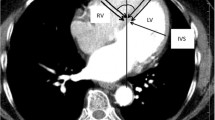

Non-invasive ventricular epicardial activation maps were acquired using 252 electrode high-resolution ECG mapping system (ecVUE, CardioInsight Technologies Inc., Cleveland, OH). Body surface potentials were collected from the 252 electrodes positioned around the thorax supported in a single-use vest; following this, a thoracic computer tomography (CT) scan was performed in order to orientate each electrode to the epicardial shell. Subsequent to segmentation of the cardiac silhouette and the electrode positions from the thoracic CT images, 1500 unipolar electrograms were reconstructed as previously described [12].

2.3 Data analysis

The raw data was analysed with ecSYNC software (CardioInsight Technologies Inc., Cleveland, OH) in order to derive 4 key activation metrics: VVtat (global biventricular total activation time); VVsync (global left/right ventricular electrical synchrony); LVtat (left ventricular total activation time); LVdisp (global left ventricular dispersion of activation) (see supplementary material for further information). The activation wave front angle was assessed from a screenshot of the isochrone maps for intrinsic and RVP with the cardiac shell orientated in a left anterior oblique cranial view where the basal to apical distance was maximal. The wave front angle was measured using an on-screen protractor application over each activation map screenshot (Protractor version 10.0, Softlibs) (Fig. 1). The angle measured was a user-selected most prominent isochrone line on each individual; as the cardiac geometry for the intrinsic and RVP activation maps are identically aligned, each patient’s LBBB map generates a reference wave front angle for RV pacing; the same isochrone was selected when comparing between intrinsic and RVP. The investigator was blinded for which patient and whether paced or intrinsic for each pair of maps. In order to define the final American Heart Association segments (16 segment model) to be activated, these final segments had to contain the latest isochrone on the activation map; in total, 30 isochrones were present on each map. For each patient on the intrinsic and the RVP map, there can be more than one segment which contains the final isochrone.